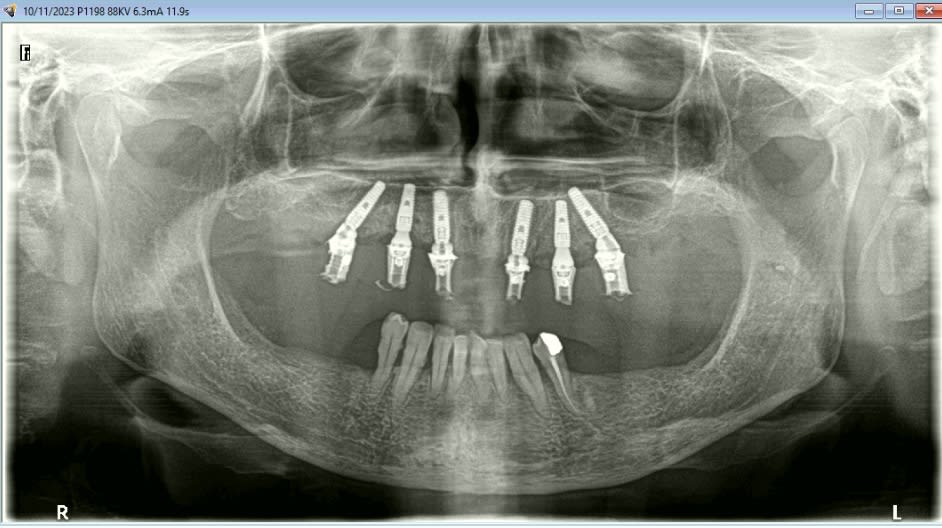

Mais celui la est tout chaud ( de vendredi dernier ) et j'ai regarder le temps que j'ai mis ( beaucoup plus complexe, donc plus long ). on va l'appeller Cas 2.

3 h de planif, modélisation du guide, puis 2 h environ pour la simulation de la chir , le modelisation et l'impression du bridge, qui tombe pile, zero retouche occlusale.

Avec un plan de traitement qui est suceptible de débat :)

K6kpgtkjnab9c7k5g9g0farlwmd6 - Eugenol

Le cone beam prévu : all on 4 et 4 implants en bas qui seront posé dans 3 semaines.